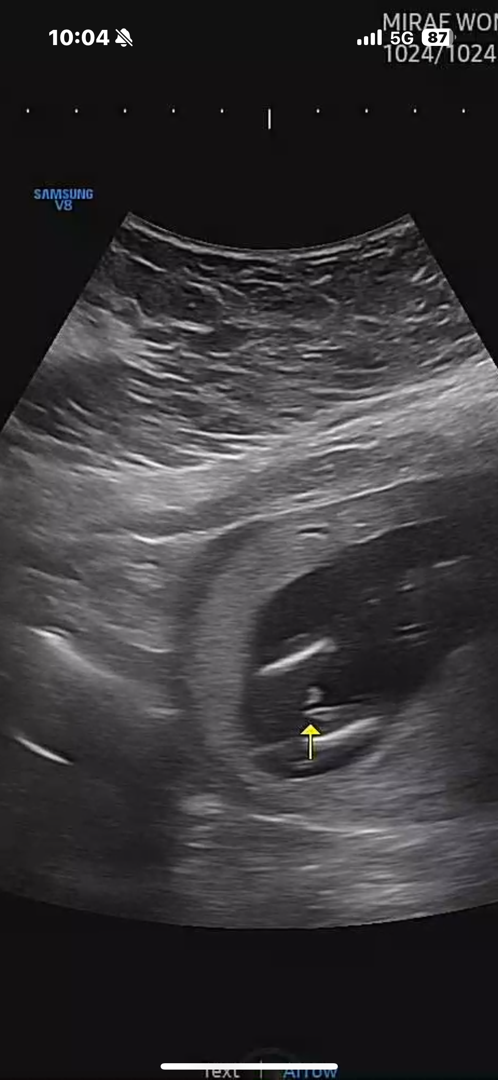

14주5일 빼박일까요?

반전 기대하면 안되겠죠..?ṑṑṑ ..ㅋㅋ..